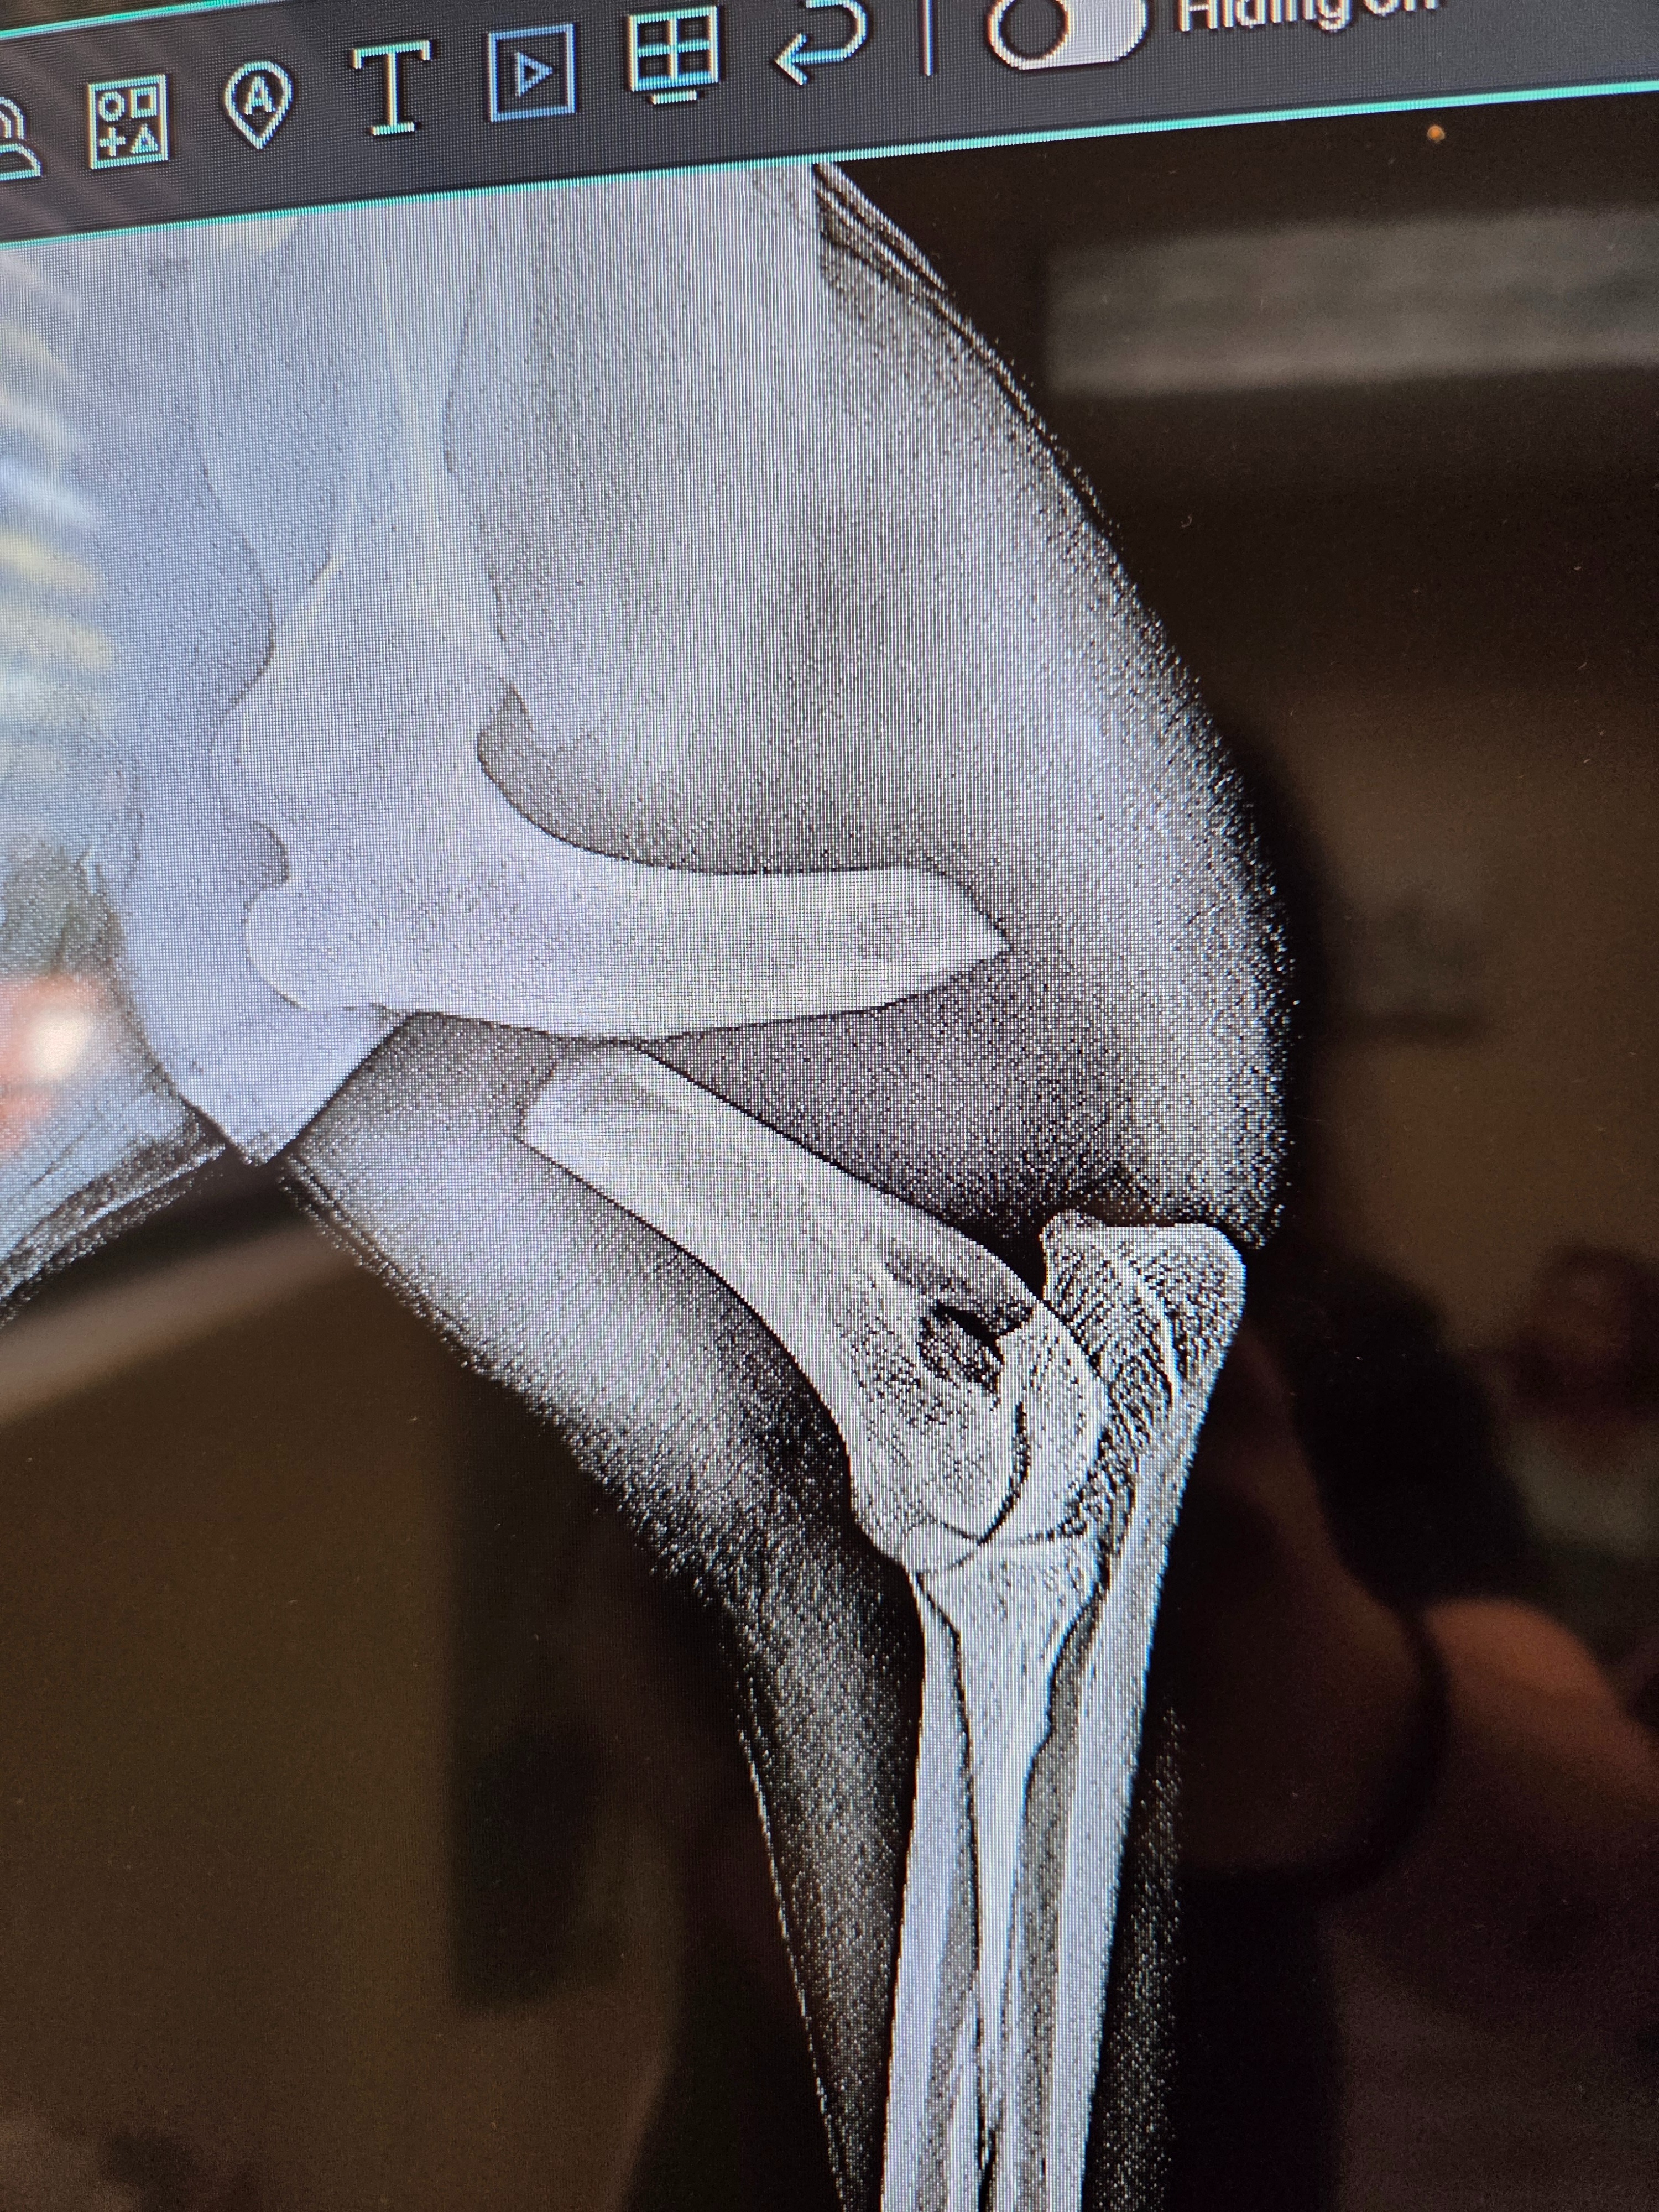

His leg was broken. Not sprained. Broken.

That was the Monday after we got him that we found out. Our little buddy needed a pin and a plate. They said we had about a week to get him in for surgery before amputation could be looked at as a solid possibility. So we vowed that matter what it takes, our sweet Marlow is not losing that leg.

His first surgery was Saturday the 21st with a follow-up surgery on the 24th to adjust the pin in his arm. Both went insanely well and he has nothing but an amazing outlook and life ahead of him!